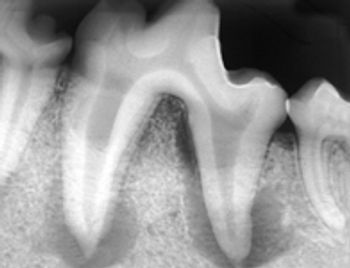

As a small-animal practitioner, you spend a good portion of your day diagnosing and treating periodontal disease. Unfortunately, due to differences in salivary pH, our patients accumulate plaque and develop calculus five times faster than people. Research shows that 80% of dogs and 70% of cats show signs of gingival disease by the age of 3 according to the American Veterinary Dental Society. Periodontal disease can cause halitosis and pain and may be related to kidney and heart disease.

At least 10-percent bone loss must be present to notice periapical disease radiographically.